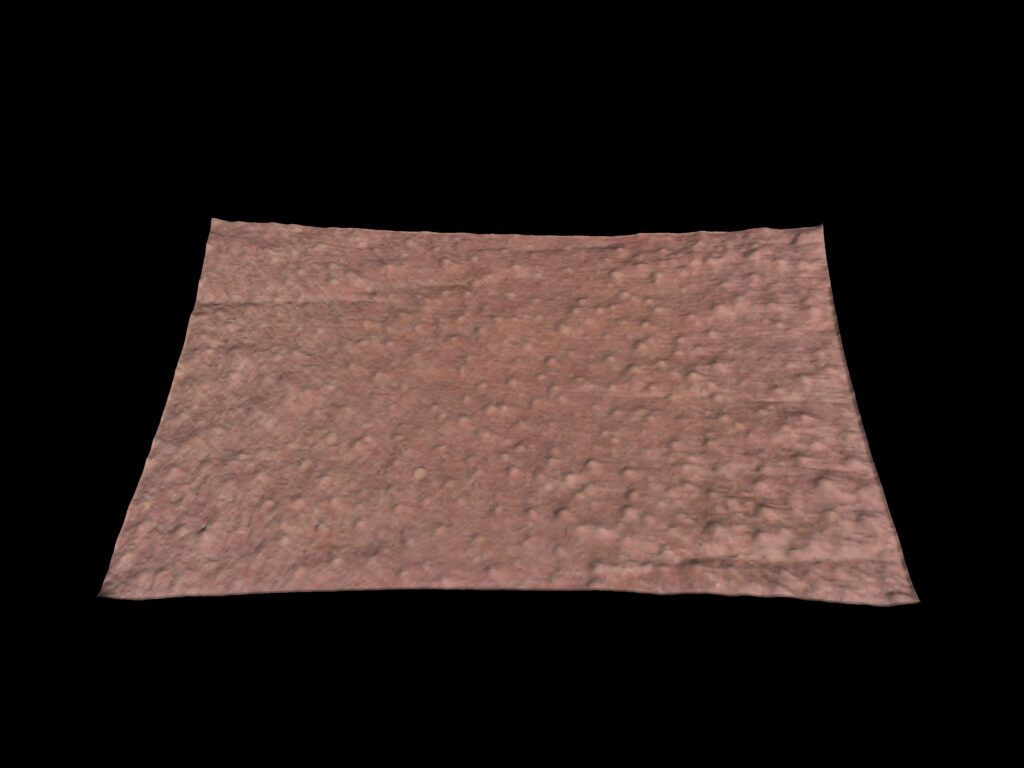

Évaluation de la rugosité

Le C-Cube est indéniablement la meilleure option pour évaluer les changements les plus subtils. Au-delà de la mesure de l’élévation des boutons, il est capable d’observer de très petits signes d’acné avant qu’ils ne s’aggravent avec l’inflammation. Cela revient à mesurer la texture de la peau, invisible à l’œil nu.

Cela peut fournir des informations sur les futurs kystes susceptibles de s’enflammer dans les jours qui suivent.